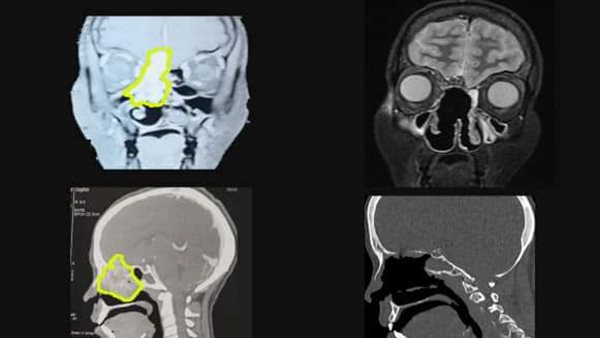

حضرت المريضة من الوادي الجديد إلي مستشفي أسيوط الجامعي تعاني من نزيف شديد بالأنف وبعد إجراء الفحوصات والإشاعات اللازمة تبين وجود ورم دموي نادر بالأنف والجيوب الأنفية يمتد الي داخل المخ وتقرر إجراء تدخل جراحي طارئ لإستئصال الورم بالكامل وترقيع قاع الجمجمة بإستخدام المنظار الجراحي بواسطة فريق جراحات مناظير قاع الجمجمة .